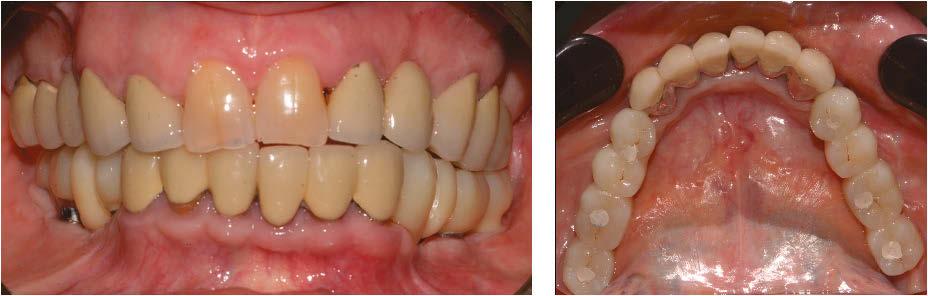

Figure 8 (left): The Panthera SUB implant is gripped to facilitate insertion without damaging it. Figure 9 (right): Positioning the implant and checking its fit (occlusal view)

Figure 6 (left): Preoperative situation, panoramic radiograph and intraoral photo. Figure 7 (right): Incisions and flap detachment